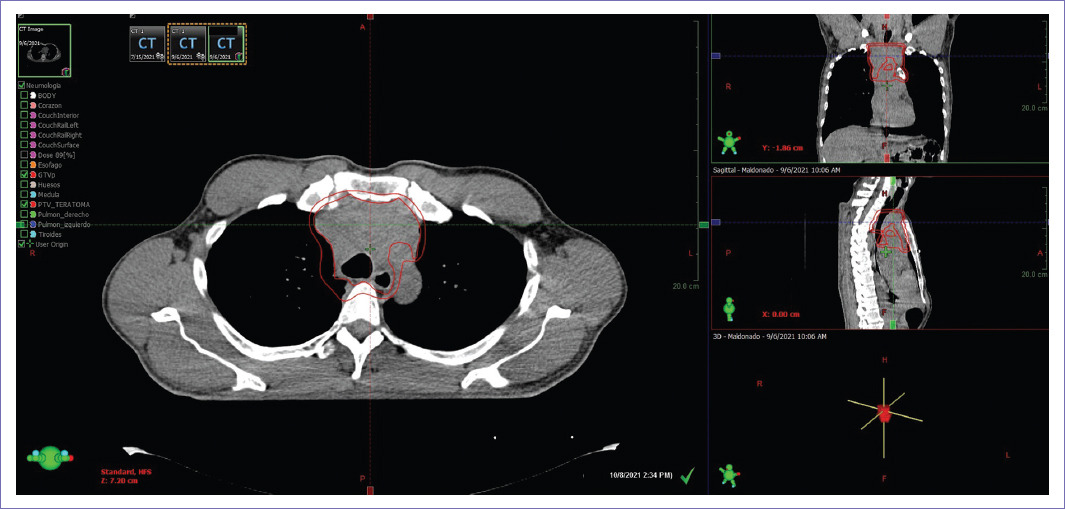

Paciente de sexo masculino de 55 años, dedicado a actividades agrícolas, con antecedente de exposición a pesticidas, fertilizantes y herbicidas. Niega consumo de alcohol o tabaco. Resto de antecedentes sin relevancia para el caso. Se valoró a paciente con antecedente de dos años con accesos de tos no productiva, que exacerbaba a la ingesta de líquidos, así como pérdida ponderal de 40 kg de peso. Previamente valorado por neumología, con tomografía computarizada (TC) de tórax realizada en junio de 2021 (Fig. 1), con reporte de tumor mediastinal, y dos tomas de biopsia con reportes histopatológicos no concluyentes. En julio de 2022 se realizó tercera toma de biopsia del tumor mediastinal, guiada por tomografía que reportó tejido muscular infiltrado por neoplasia con diferenciación cartilaginosa, con morfología sugerente de neoplasia benigna, a considerar teratoma. En agosto de 2021, se sesiona caso multidisciplinariamente y se considera irresecable, por lo que se envió a valorar manejo por radiooncología.

Figura 1 Tomografía computarizada simple y contrastada de tórax de junio del 2021. Corte axial donde se observa tumoración con densidad de tejidos blandos que envuelve el tronco braquiocefálico derecho, con oclusión subtotal.

Figura 2 Tomografía computarizada simple de tórax de planeación de radioterapia de octubre del 2021 correspondiente con contorno de volumen de tratamiento, en la cual se observa tumoración mediastinal de densidad tejidos blandos, con ensanchamiento mediastinal en eje lateral.